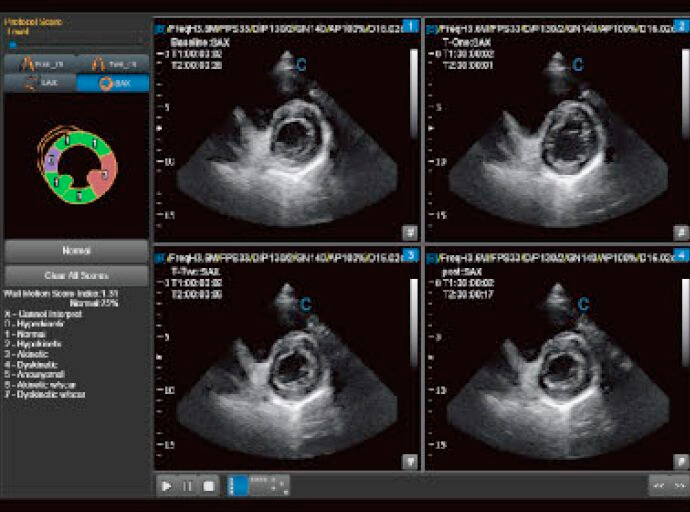

Stress d'écho

- Aide à confirmer ou à exclure la présence d'une maladie coronarienne.

- Les patients présentant des blocages de l'artère coronaire peuvent ou non présenter des symptômes minimes au repos.

- Symptômes pouvant être découverts en soumettant le cœur au stress de l'exercice.

Surveillance ventriculaire gauche (VG)

- Une nouvelle méthode non invasive d'évaluation globale du ventricule gauche.

- Analyse le fonctionnement local du ventricule.

- Outil de contrôle et de suivi entre professionnel/patient